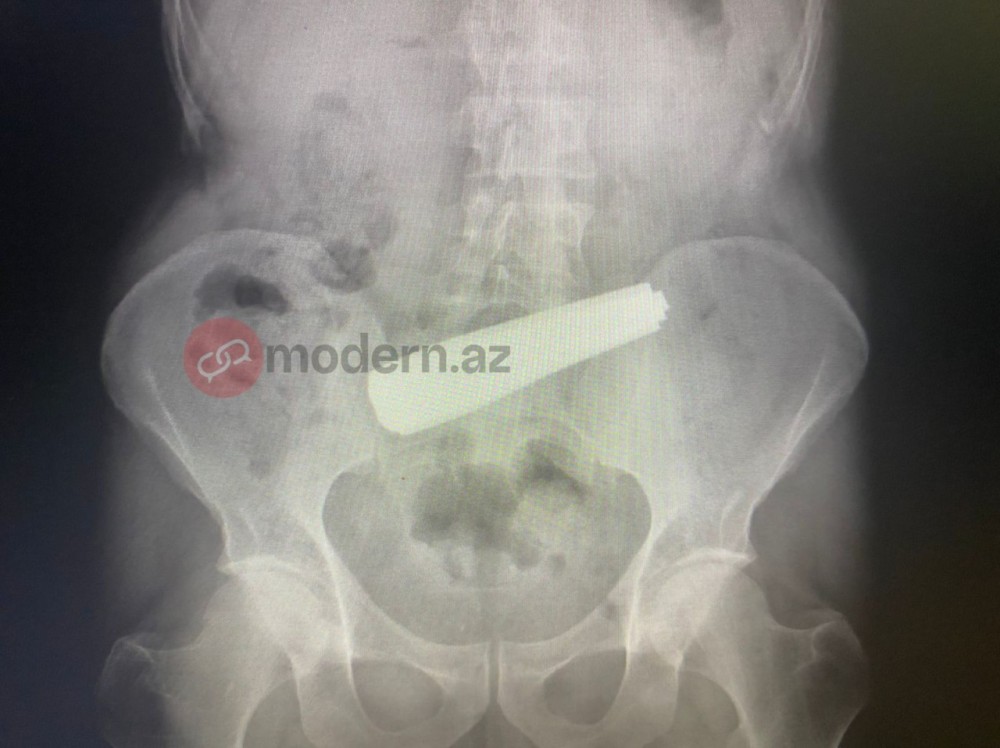

Bakı sakini 9 ədəd qaşıq uddu - FOTOLAR

Bakıda bir nəfər 9 ədəd qaşıq udub.

İlkin məlumata görə, bir nəfərin bir neçə metal qaşıq udduğu bildirilib. Lakin xəstə bir neçə tibb müəssisəsi tərəfindən qəbul edilməyib.

Məlumata görə, xəstə 9 ədəd metal qaşığı udub. Həkimlər tərəfindən həyata keçirilən əməliyyat uğurla başa çatıb.